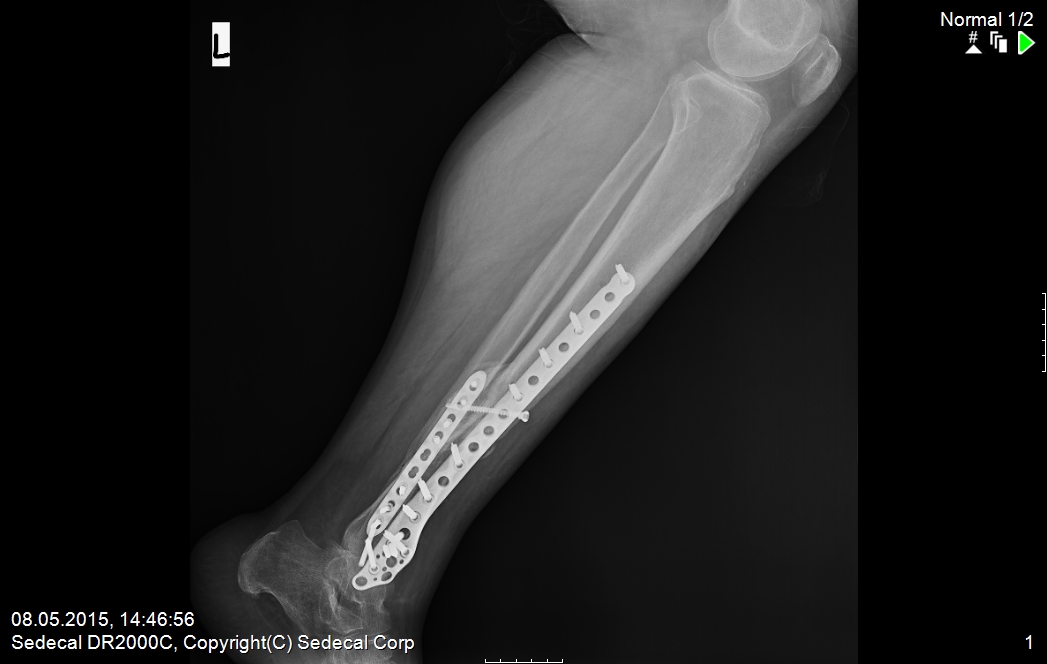

11 Şub Parçalı tibia (kaval kemiği) kırığı by admin in TRAVMA (KIRIK-ÇIKIK) VAKA ÖRNEKLERİComments ameliyat öncesi 1 ameliyat öncesi 2 ameliyat sonrası 2 ameliyat sonrası1